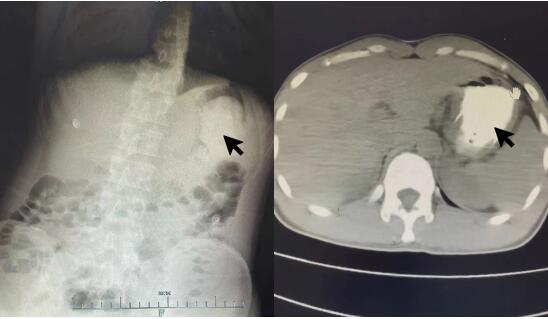

患者接触史明确,诊断为“磷酸铵盐干粉灭火剂中毒”。入院后禁食,胃肠减压,给与保护胃黏膜、抑制胃酸分泌、保护肝功能、导泻、水化碱化以及营养支持对症治疗。根据每日血清电解质结果调整补充量。约1 d后,血磷、血钾、碱剩余恢复正常范围,腹部CT:结肠内高密度影(见图 2)。心脏、双下肢静脉、腹部及泌尿系B超未见明显异常。2 d后外周血白细胞数恢复正常范围。肺部CT示右肺下叶少许炎性灶。3~4 d后血钙、肌酸激酶同工酶、超敏C反应蛋白恢复正常范围。头颅CT及MRI未见明显异常。脑电图示轻中度异常,右侧额颞部中央部略偏胜,脑地形图示右侧额颞部中央部δ频段功率相对偏高。考虑患者口咽部疼痛较前缓解,粪便隐血转阴,改为半流质饮食。5 d后,肌酸激酶恢复正常范围。食管CT:食管局部管壁稍水肿增厚,管腔狭小(见图 3)。患者住院期间未使用抗生素,转氨酶、肌酐均在正常范围,予第6天出院。本病例报道经浙江大学医学院附属第一医院伦理委员会批准,且所有临床资料均获得患者本人授权(伦理审批号:2022380)。

| 图 3 患者入院5 d后食道CT平扫示食管局部管壁稍水肿增厚,管腔狭小 |